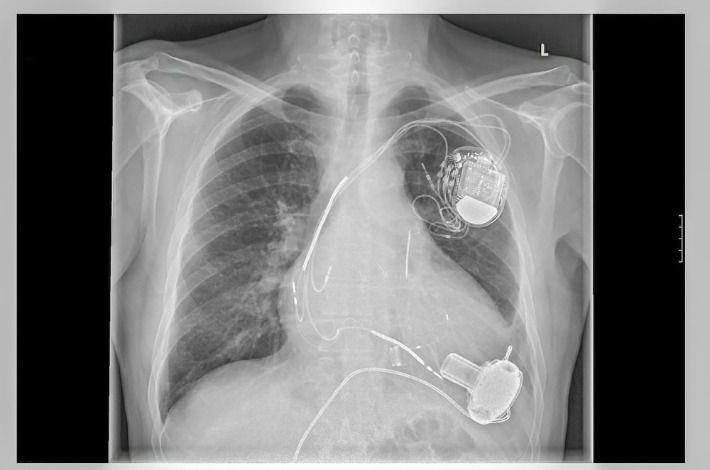

השתלת קוצב לב (Pacemaker Implantation)

קוצב לב הוא מכשיר אלקטרוני שתפקידו לשלוח אותות חשמליים ללב בכדי לדאוג שיפעם בקצב סדיר. הלב מתפקד כמשאבה עשויה שריר, אשר נשלטת ע"י אותות חשמליים שמקורם בתאים מיוחדים בלב. הפרעה של אותות חשמליים אלו, מביאה לקצב לב איטי מדי או מהיר מדי, או לפעימות לא סדירות של קצב פעימות הלב, מה שמצריך השתלת קוצב לב חיצוני. השתלת קוצב לב היא תהליך פשוט יחסית: המחולל מושתל מתחת לעור ליד עצם הבריח בצד השמאלי של החזה. בדרך כלל המחולל מחובר ללב דרך כלי דם ראשי באמצעות סיב אלקטרוני גמיש .

• קוצב לב -דו-לשכתי (קוצב לב רגיל) – תפקידו להגביר קצב לב איטי, כאשר שתי אלקטרודות מוחדרות ללב, אחת בעליה ואחת בחדר (בחלקו העליון והתחתון של הלב).

• קוצב לב דו-חדרי - משמש לטיפול בחולים עם אי ספיקת לב חמורה. הקוצב מחובר עם שלוש אלקטרודות: אחת לעליה הימנית, שנייה לחדר הימני ושלישית ממוקמת בחדר השמאלי של הלב.

• דפיברילטור - סוג נוסף ומשוכלל של קוצב לב, שתפקידו לשלוט בקצב לב מהיר שיכול להוביל לדום לב. מערכת זו מושתלת באופן דומה לזה של קוצב לב רגיל. המערכת מנתרת את קצב הלב, וכאשר מזוהה הפרעת קצב מהירה, נשלח שוק חשמלי ללב אשר מחזיר את קצב פעימות הלב לקצב סדיר .

ניתוח השתלת קוצב לב מבוצע בחדר צנתורים תחת הרדמה מקומית. חדר הצנתורים הוא חדר סטרילי המכיל את המכשור הנדרש לשם ביצוע הפעולה. מדובר בניתוח קטן יחסית, שבמהלכו מבוצע חתך באורך של מספר סנטימטרים, בדרך כלל באזור החזה הסמוך לכתף. לאחר ביצוע החתך, מוחדרת אלקטרודה או אלקטרודות, תלוי בסוג הקוצב המושתל, לתוך וריד הנמצא סמוך לאזור ההשתלה, ומשם ללב. על-מנת למצוא את המיקום המתאים לאלקטרודות, נעשה שימוש בין היתר במכשיר רנטגן הנמצא בחדר הצנתורים.